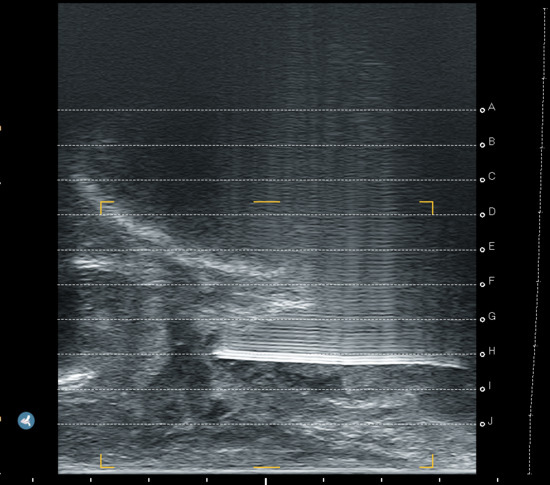

We prospectively assessed the tolerability and operational effectiveness of transperineal MRI-targeted biopsies under pure local anaesthesia with a prospective, monocentric, mono-operator cohort of transperineal prostate biopsies. Patients were assigned for biopsies according to clinician decision following the “MRI pathway” [5] from our urological consultation in Godinne University Hospital (Yvoir, Belgium). This study was conducted between late January 2024 and late May 2024. The decision for local anaesthesia or sedation was made after discussion between the patient and the urologist, aiming to assess our current process of selection for biopsies. Out of 51 patients, 34 received local anaesthesia, whereas 17 opted for sedation. The prostate biopsies took place in a daycare clinic operative room, with the help of 1 nurse. If the biopsy was performed under sedation, an anaesthesiologist was present. Sedation was performed using propofol. No fasting was required for patients under local anaesthesia, whereas patients undergoing sedation had to observe a 6 h fast. All of our biopsies were performed transperineally, with image-based MRI-US elastic fusion using the Koelis Trinity® platform (Koelis, Meylan, France), and following the MUSIC (Michigan Urological Surgery Improvement Collaborative) pattern. We targeted 3–4 biopsy cores for each MRI target lesion with a PIRADS score ≥4 or a PIRADS score of 3 with PSA density > 0.15 ng/mL/cc. In case of a mix of PIRADS 4–5 and 3 lesions, only PIRADS 4–5 were targeted. A preoperative urine analysis was performed to rule out bacteriuria. No antibiotic prophylaxis was used based on recent RCT [17] and local experience. The patient was placed in the lithotomy position and asked to self-retract the scrotum with the hands. We used cutaneous disinfection with a povidone–iodine solution and performed local anaesthesia with 20 mL Linisol 2% diluted with 20 mL NaCl 0.9%. We first performed a superficial anaesthesia with 20 mL of anaesthetic solution with a 21 G needle in a fan-shaped pattern from the median raphe down to each side to the anal margin (Figure 1). After the superficial anaesthesia, we performed MRI contouring on the Koelis Trinity® software Promap 4.3.0. Then we performed prostatic/deep anaesthesia under transrectal ultrasound control with 10 mL of anaesthetic solution for each side, targeting the posterior–apical plane with the outer shaft of an 18 G biopsy needle (Figure 2). Once both superficial and prostatic anaesthesia were performed, transrectal ultrasound image acquisition, contouring, and image fusion were performed. After a short waiting period, prostate biopsies were performed using a 22 cm 18 G coaxial needle and a BD Magnum™ biopsy gun (Becton, Dickinson and Company, Franklin Lakes, NJ, USA).

Figure 1. Superficial local anaesthesia in “fan shape” (arrows and line).